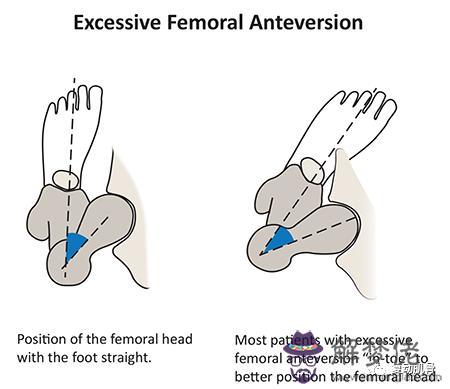

(一)股骨前傾

股骨前傾是造成3歲以上兒童步態異常最常見的原因,它是由股骨內旋引起的。到了12歲時,骨骼才會逐漸保持穩定的狀態。從12-16歲開始,隨著成年年齡的增長,這種變化會減小

標志和癥狀

1.內八步態,孩子開始上學時更加明顯

2.站立位時,雙側髕骨出現內翻

3.走路時,膝蓋出現內扣

▶1.股骨與脛骨之間的旋轉角度逐漸變小,通常到了12歲會有所緩解,同時家長需要經常觀察孩子的膝蓋和腳的位置變化。

▶3.如果病情比較嚴重(內旋角度大于80度,外旋小于10度)并且伴有跌倒或嚴重的體態問題,則可以考慮在10歲以后進行手術。